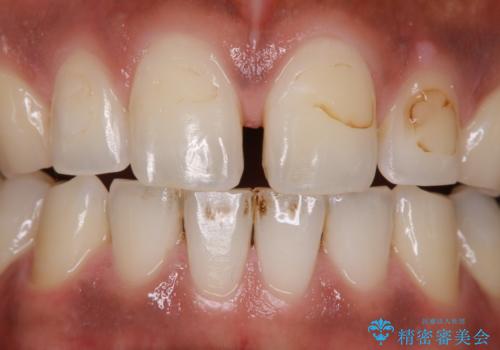

ホワイトニング後は、ホワイトバンドや白い斑点がでることがあります。

その場合、追加でオフィスホワイトニングを行うことや、ホームホワイトニングの併用を行うことで、均一な白さに近づけることができます。